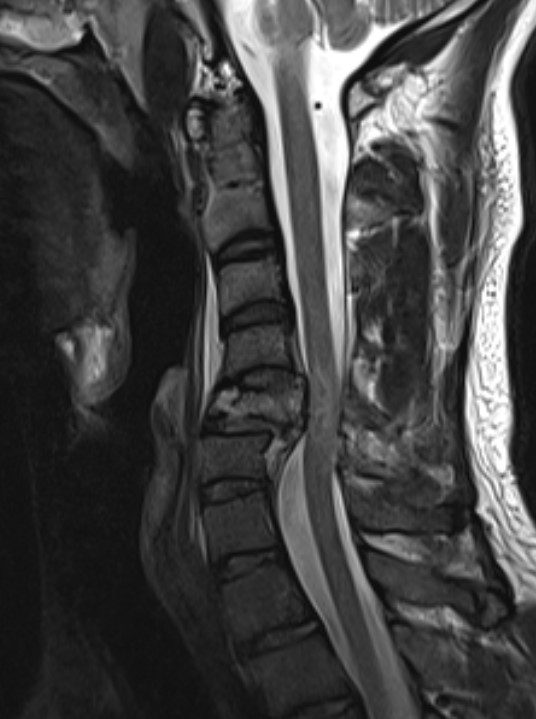

MRI images demonstrating spinal cord injury and posterior ligamentous injury

Assess integrity of posterior column

Evaluate cord injury